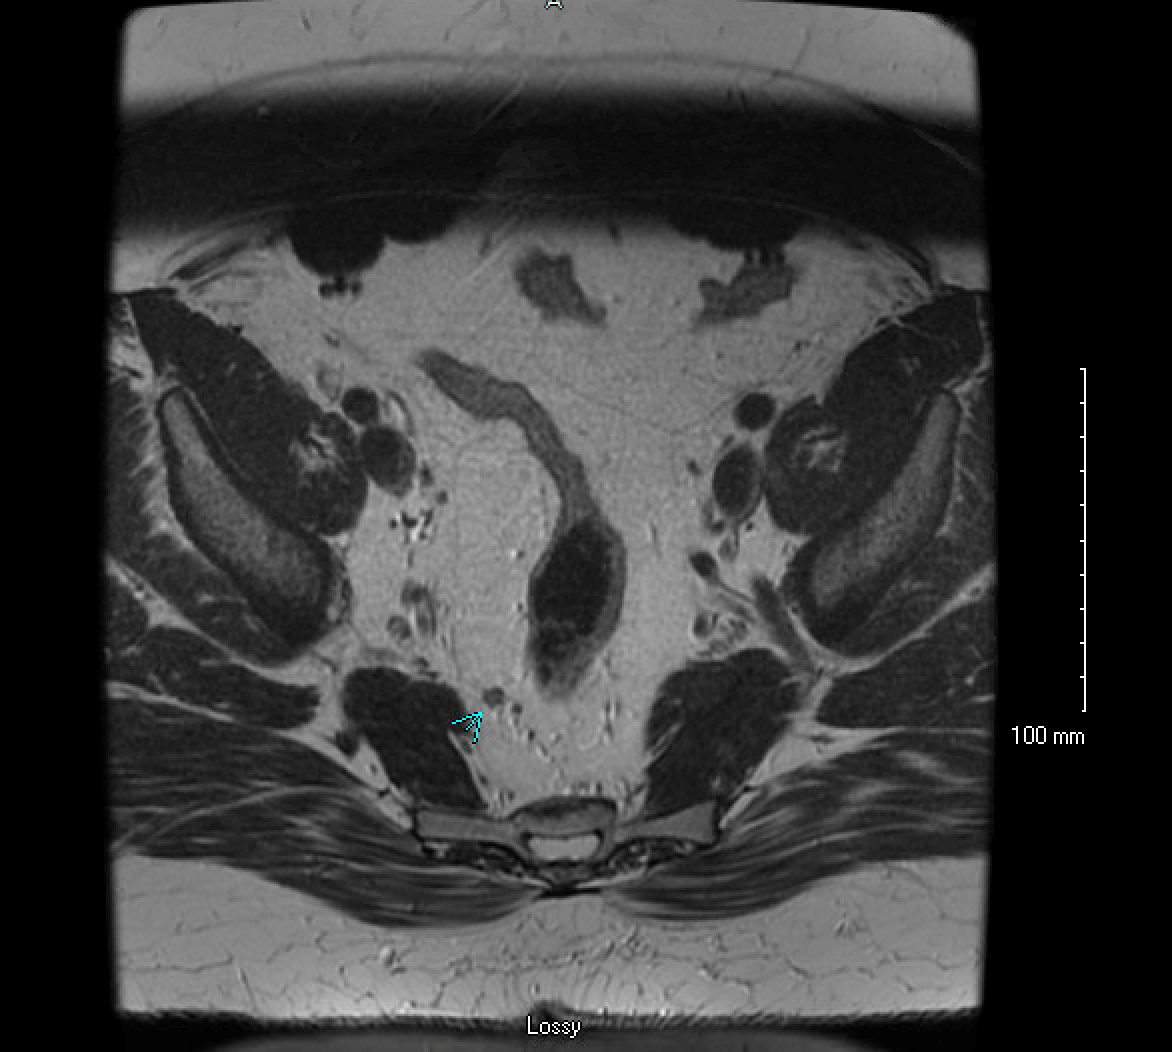

First and foremost, it is important to remember that this is a cancer and it should be staged appropriately. The most common malignant polyps contain cancer cell type called adenocarcinoma. The work-up for these includes computed tomography (CT) scan of the chest, abdomen and pelvis along with carcinoembryonic antigen (CEA) level. Importantly, if the area has not been marked colonoscopically with an intraluminal tattoo this should be done. Preferably this is done within the first 2 weeks when the scar is still visible. If the malignant polyp is within the rectum, local staging is also indicated. This is performed utilizing an endorectal ultrasound (EUS) or rectal protocol magnetic resonance imaging (MRI), Figure 1. It is important to note that these pelvic imaging tests are specialized. Many medical centers do not have the capability to perform specialized rectal protocol MRI or the expertise to perform endorectal ultrasound. If there is any question as to testing to be ordered for rectal cancer, consultation with a colorectal surgeon is encouraged.